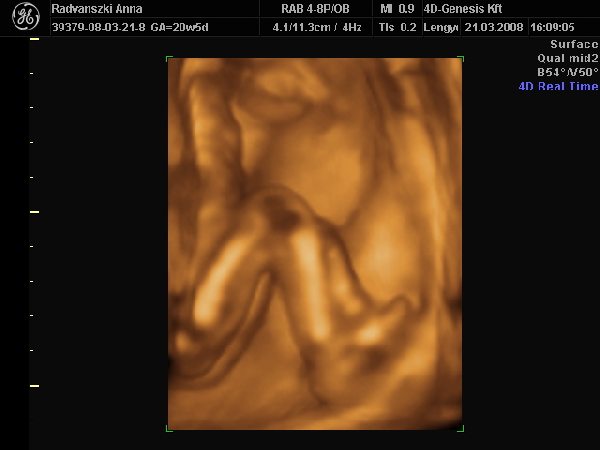

Még múlt 7pénteken elmentünk végül is 4D-re. Nagy élmény volt, bár aznap reggelre éreztem, hogy fejenállásba ment át a picur, mert felül a köldökömnél rugdosott. Így aztán az UH-n elég sokat kellett vadászni, hogy jól látszodjon a kis pofija, de a hölgy nagyon türelmes volt. Úgy 50percet vizsgált, közben csokiztunk is egy kicsit, hátha azzal nagyobb mozgásra késztetjük a pöttömöt. Hát sikerült is, mert megpróbálkozott egy bukfenccel. Szegényke nagyon taposott a kis lábaival :D , a fejét meg tisztára maga alá görbítette, de a talpa mindig megcsúszott a méhfalon, így nem sikerült neki a produkció. De azért sikerült egy kicsit kijjebb kecmeregni e magát, így aztán néhány viszonylag jól látható képet is tudtak róla készíteni.

Megnézték mindenét, mindene nagyon szép és rendben van, makk egészségesnek tűnik. :lol:

És m egint azt mondták, hogy kislány. Mondjuk a beterpesztés elmaradt, de nézte a néni 2d-vel, 3D-vel is, és azt mondta, hogy nincs a lába között semmi :lol:

Íme egy pár kép a kiscsajszinkról :D :